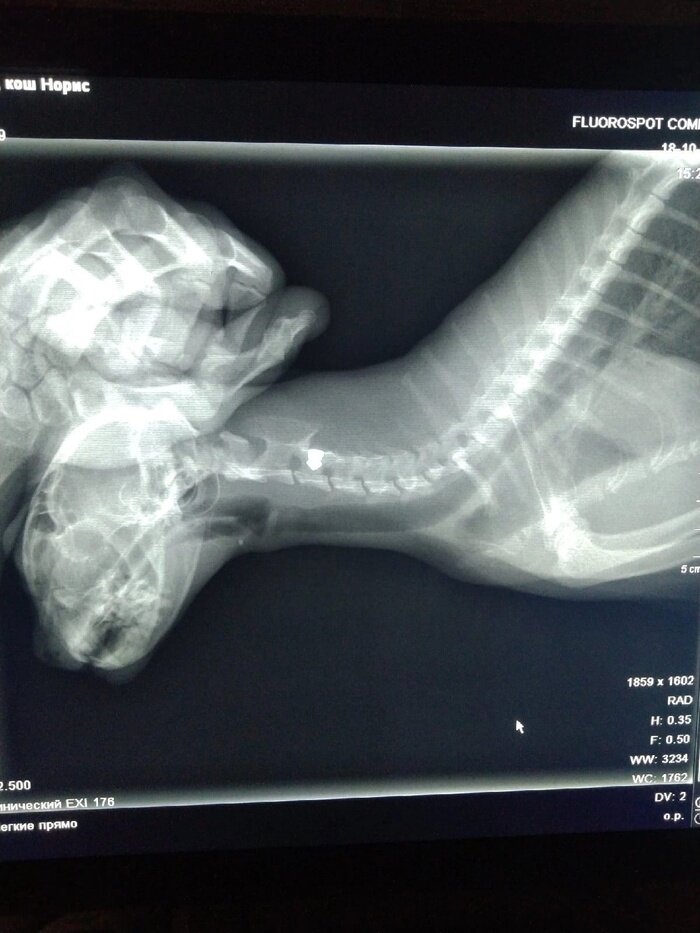

Прошлой зимой в приют поступила бывшедомашняя кошка, подброшенная к подвалу. Внешне целая, никаких ран. Случайно нащупали маленькое, жесткое и еле заметное образование возле холки. Оказалась - пуля. Кошку прооперировали, пуля застряла неглубоко, ничего не повредила. Кто и зачем в не стрелял, остаётся загадкой Миссис Норрис выглядит немного недовольной после операции, но собой явно гордится

Прошлой зимой в приют поступила бывшедомашняя кошка, подброшенная к подвалу. Внешне целая, никаких ран. Случайно нащупали маленькое, жесткое и еле заметное образование возле холки. Оказалась - пуля.

Кошку прооперировали, пуля застряла неглубоко, ничего не повредила. Кто и зачем в не стрелял, остаётся загадкой